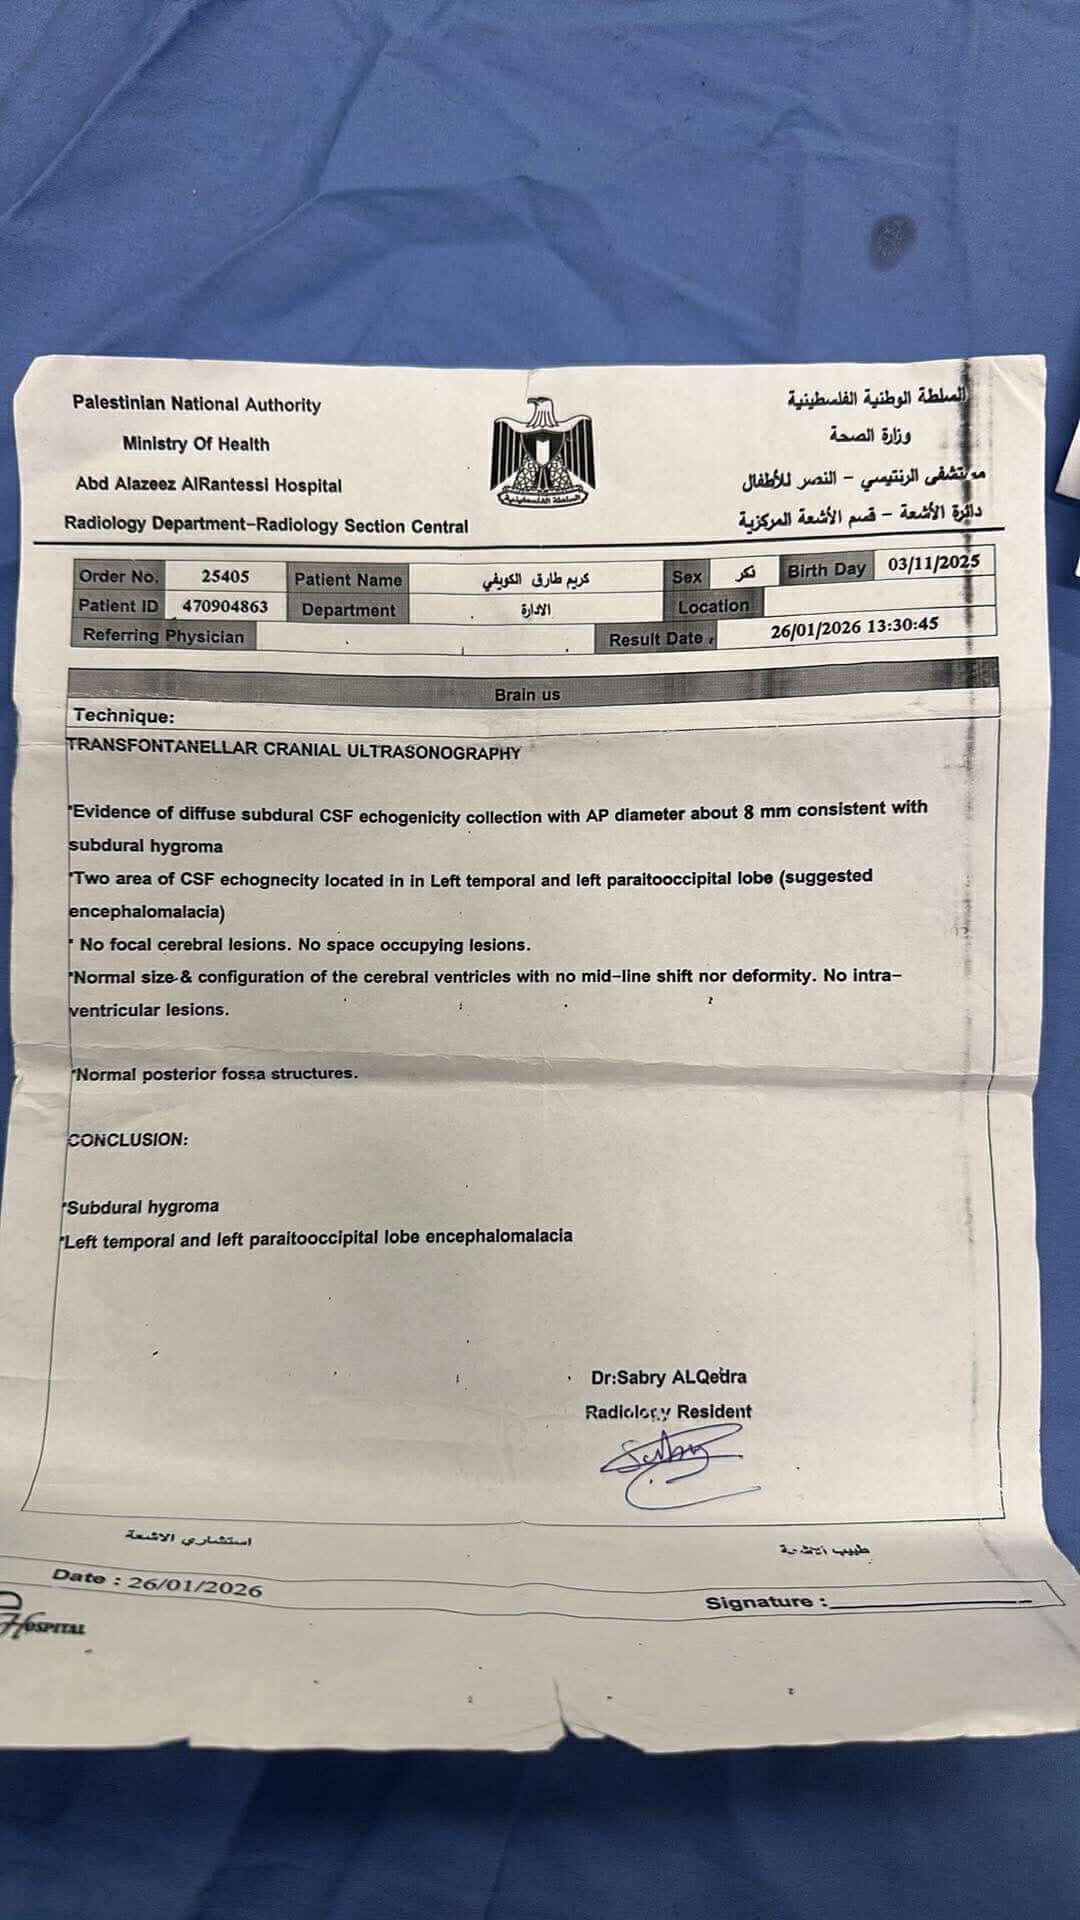

A 3-month-old baby in my family is facing a life-threatening brain condition. Medical reports and imaging confirm serious neurological injury that requires immediate, specialized treatment outside Gaza—care that is not available here.

Without urgent medical intervention, this baby is at high risk of:

• Permanent brain damage

• Severe developmental delays

• Seizures and lifelong disability

• Or loss of life